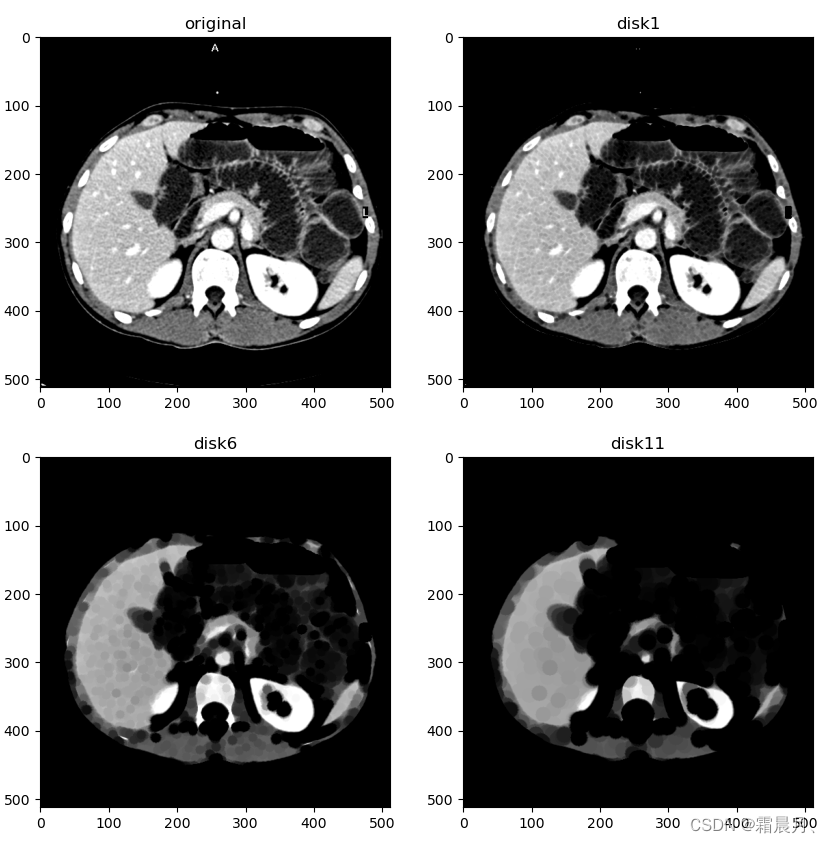

不同大小的核腐蚀(disk)

selem = square(5) #square(2) # #square(4) #disk(6)

eroded = erosion(im, selem)